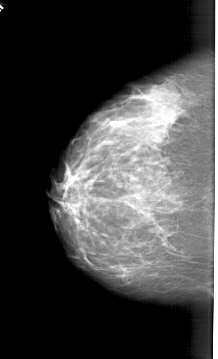

A_1394_1.LEFT_CC

LEFT_CC LINES 5731 PIXELS_PER_LINE 3481 BITS_PER_PIXEL 12 RESOLUTION 43.5 NON_OVERLAY